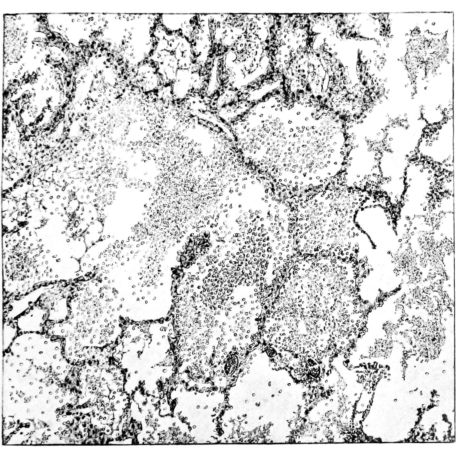

FIG. II. AUTOPSY NO. 98. DRAWING OF A SECTION THROUGH A TRACHEA SHOWING NECROTIZING HEMORRHAGIC INFLAMMATORY PROCESS OF THE MUCOSA.

The changes are less marked, perhaps, in the trachea than in its finer ramifications. The mucosa is constantly more or less destroyed and large areas, usually focal, are entirely devoid of their epithelial covering. This is replaced by a sparse exudate, composed largely of red blood cells, mucus, a small amount of fibrin, and nuclear fragments (Fig. II). It may dip into the submucosa for a short distance, but usually these indentures are associated with the ducts of the mucous glands into which the inflammatory reaction extends. A more striking feature than the exudate, however, is the edema and the congestion of the submucosa. The loose areolar tissue of the submucosa is spread widely apart, and throughout it distended blood vessels are very conspicuous. Occasionally such a vessel is broken and actual hemorrhage appears in the submucosa. Occasionally, too, the inflammation extends down the duct to the mucous gland itself, and here, also, aplastic inflammatory reaction is evident, inasmuch as the acini now stain intensely red with the cells undifferentiated from each other and specked here and there by broken remains of the dead nuclei (Fig. III). After the disease has continued for a short period, even at the end of five or six days, some regeneration of the epithelial lining may be seen (3) (Fig. IV). But despite this, the acute picture persists, and there goes on, side by side, an attempted repair characterized by epithelial regeneration and the same evidence of acute change. Since the lesion is essentially a superficial one, scars or contractures of any extent are not encountered in the trachea, even in examples of the disease that have ended fatally only after many weeks.[4]